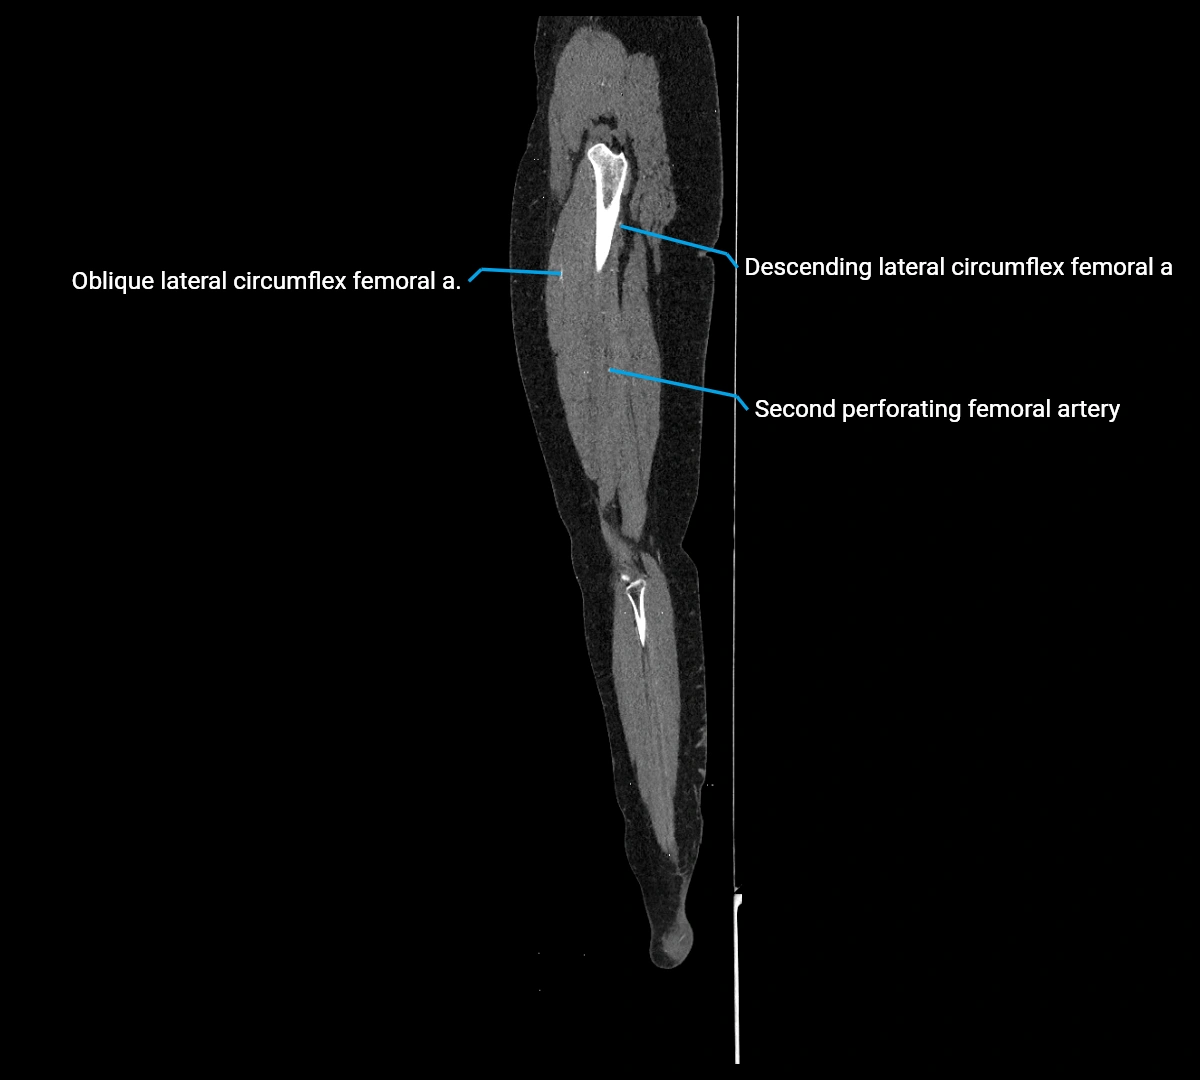

CT images

image